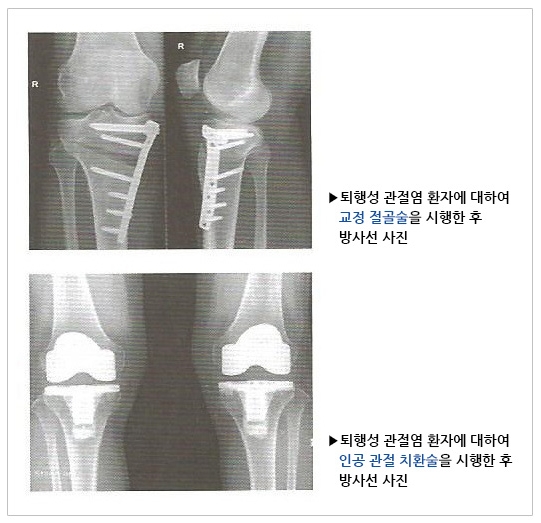

약물이나 물리치료, 행동요법 등 다른 보존적 치료 방법을 시행했음에도 불구하고 지속적으로 증상이 있는 환자는 궁극적으로 수술적 치료를 요하게 됩니다.

관절염의 치료에는 다양한 수술적 방법이 있으며 의사와 환자는 충분한 진찰과 상담을 통해 환자의 증상, 직업, 건강상태 등을 고려하여 적절한 수술적 치료법을 선택해야 합니다.